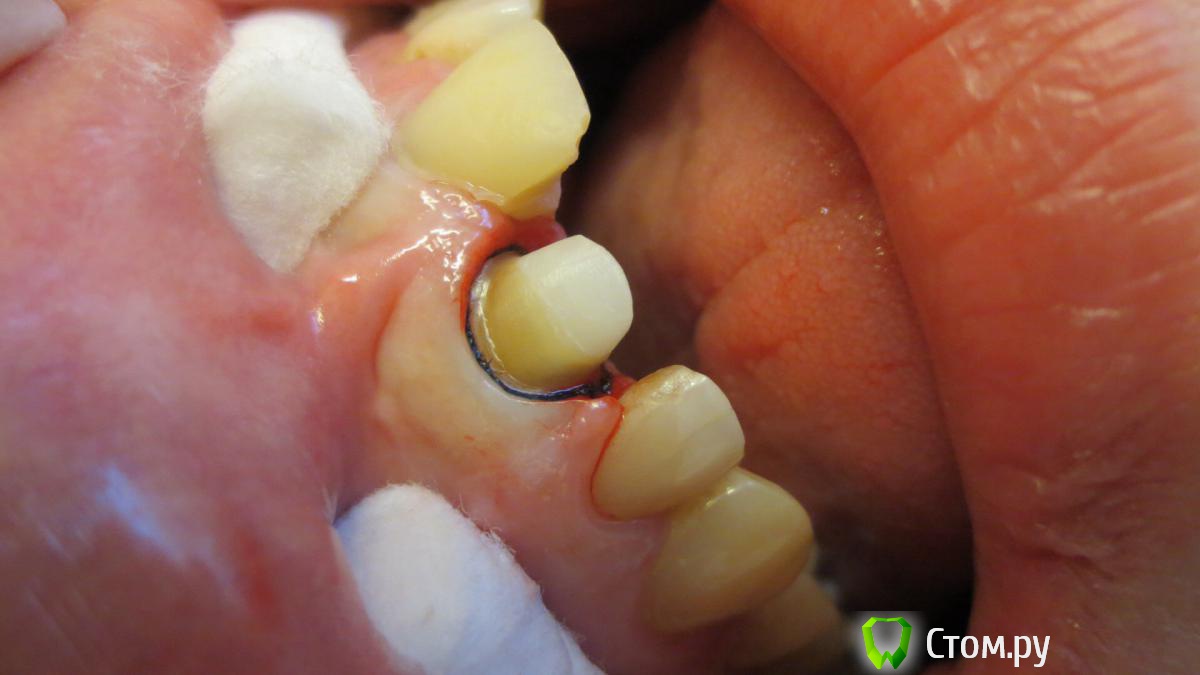

Военный Врач Опубликовано 28 февраля, 2014 Поделиться Опубликовано 28 февраля, 2014 (изменено) С позволения ТС-посмотрите коллеги и мой преп чтоб тему отдельно плодить Изменено 28 февраля, 2014 пользователем Военный Врач Ссылка на комментарий

chervoncevdaniil Опубликовано 2 марта, 2014 Поделиться Опубликовано 2 марта, 2014 С позволения ТС-посмотрите коллеги и мой преп чтоб тему отдельно плодитьПо-моему очень аккуратный преп,вы с нитью препарируете или перед оттиском ставите только? Ссылка на комментарий

oleg07 Опубликовано 3 марта, 2014 Поделиться Опубликовано 3 марта, 2014 очень красивый преп))) Ссылка на комментарий

Evikrol Опубликовано 3 марта, 2014 Автор Поделиться Опубликовано 3 марта, 2014 С позволения ТС-посмотрите коллеги и мой преп чтоб тему отдельно плодитьА не глубоко уступ? Это циркониевая вкладка? Если да то и циркониевая коронка планируется? Если так то зачем погружать уступ под десну? Ссылка на комментарий

k.t.m. Опубликовано 3 марта, 2014 Поделиться Опубликовано 3 марта, 2014 если под безметалл то как то перепреп,ладно тут зуб депульпированный, сепарация проведена так что срезан 1.2 Ссылка на комментарий

Военный Врач Опубликовано 5 марта, 2014 Поделиться Опубликовано 5 марта, 2014 А не глубоко уступ? Это циркониевая вкладка? Если да то и циркониевая коронка планируется? Если так то зачем погружать уступ под десну?Вкладка cosmopost Ссылка на комментарий